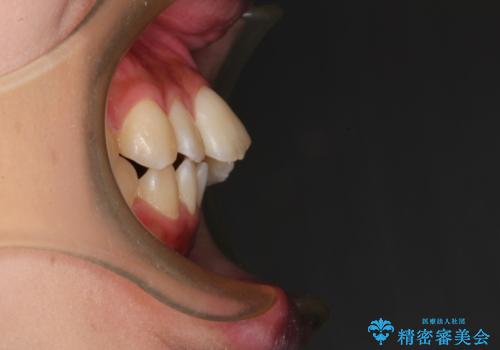

左上の前から2番目の歯が通常とは異なる形態をしており、左右対称にすることはできませんでしたが、インビザラインで周りに気づかれることなく矯正治療をおえることができ、満足していただけました。